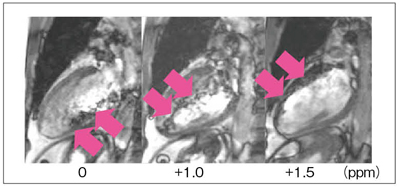

バンディングアーチファクトを減少させるもう1つの方法は,中心周波数(f0)をシフトさせることである。バンディングアーチファクトは,位相が180°ずれた場所で出現する。よって,中心周波数(f0)をシフトさせると,位相のズレ具合を変えることができる。位相のズレ具合が変わると,それに対応して画像上のバンディングアーチファクトの出現位置がずれる(図5)。心臓撮像の場合,心臓以外にバンディングアーチファクトが出現しても大きな問題にはならず,目的とする撮像領域の面積(FOV)はさほど大きくない。このため,中心周波数(f0)をずらしてバンディングアーチファクトが出現する位置をずらすことで,心臓画像への悪影響を回避することが可能になる(図6)。

図6 中心周波数(f0)をシフトした画像